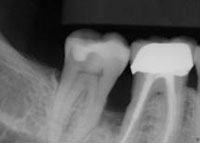

• Scaling and root planing: Deep cleaning below the gum line